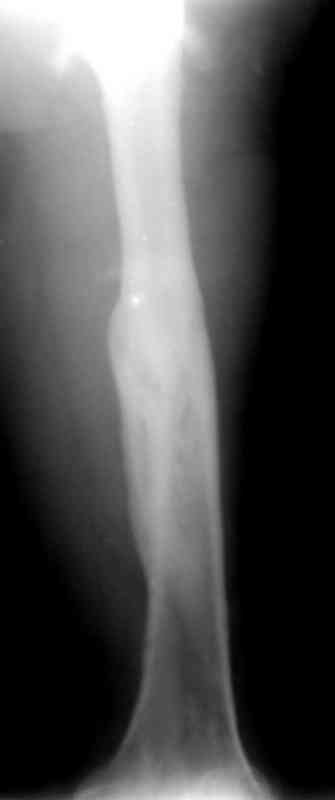

Больной А., 28 лет, поступил в НИИ им. Н.В. Склифосовского 22.12.99 после падения на улице. Жалобы на боли в области левого тазобедренного сустава и левом бедре. Из анамнеза следовало, что 20.06 во время прыжка с парашютом у него возник закрытый оскольчатый перелом средней трети левой бедренной кости со смещением отломков, по поводу чего в одной из ЦРБ Московской области через 3 дня после травмы был произведен открытый интрамедуллярный остеосинтез штифтом типа Кюнчера.

Послеоперационное течение было гладким. Больной ходил при помощи костылей с дозированной нагрузкой на оперированную конечность.При осмотре в НИИ им. Н.В. Склифосовского через 6 месяцев после травмы:

левое бедро и левый коленный сустав несколько увеличены в объеме, отечны, пальпаторно определяется болезненность в средней трети бедра;

по его наружной поверхности послеоперационный рубец - рана зажила первичным натяжением. При измерении длины бедер обнаружено укорочение левого бедра на 4,5 см. На рентгенограммах этого бедра: ось конечности правильная, отмечается захождение основных костных фрагментов по длине, проксимальный конец штифта выступает слишком медиально и высоко относительно большого вертела, периостальная мозоль незначительна.22.12 - через 6 месяцев после операции, произведенной в ЦРБ, нами по поводу замедленно консолидирующего перелома левой бедренной кости с ее абсолютным укорочением под наркозом произведена операция: удаление штифта, закрытый блокирующий интрамедуллярный остеосинтез перелома левого бедра штифтом без рассверливания (UFN) длиной 40 см, диаметром 10 мм с блокированием только проксимальных отверстий (динамический остеосинтез). Наложен аппарат Илизарова на 4 полукольцах с целью удлинения укороченного бедра. Послеоперационное течение без особенностей. Ежедневно осуществляли дистракцию отломков на 1 мм. Через 3 недели после операции больной выпи-сан на амбулаторное лечение с продолжением дистракции отломков. В течение 1,5